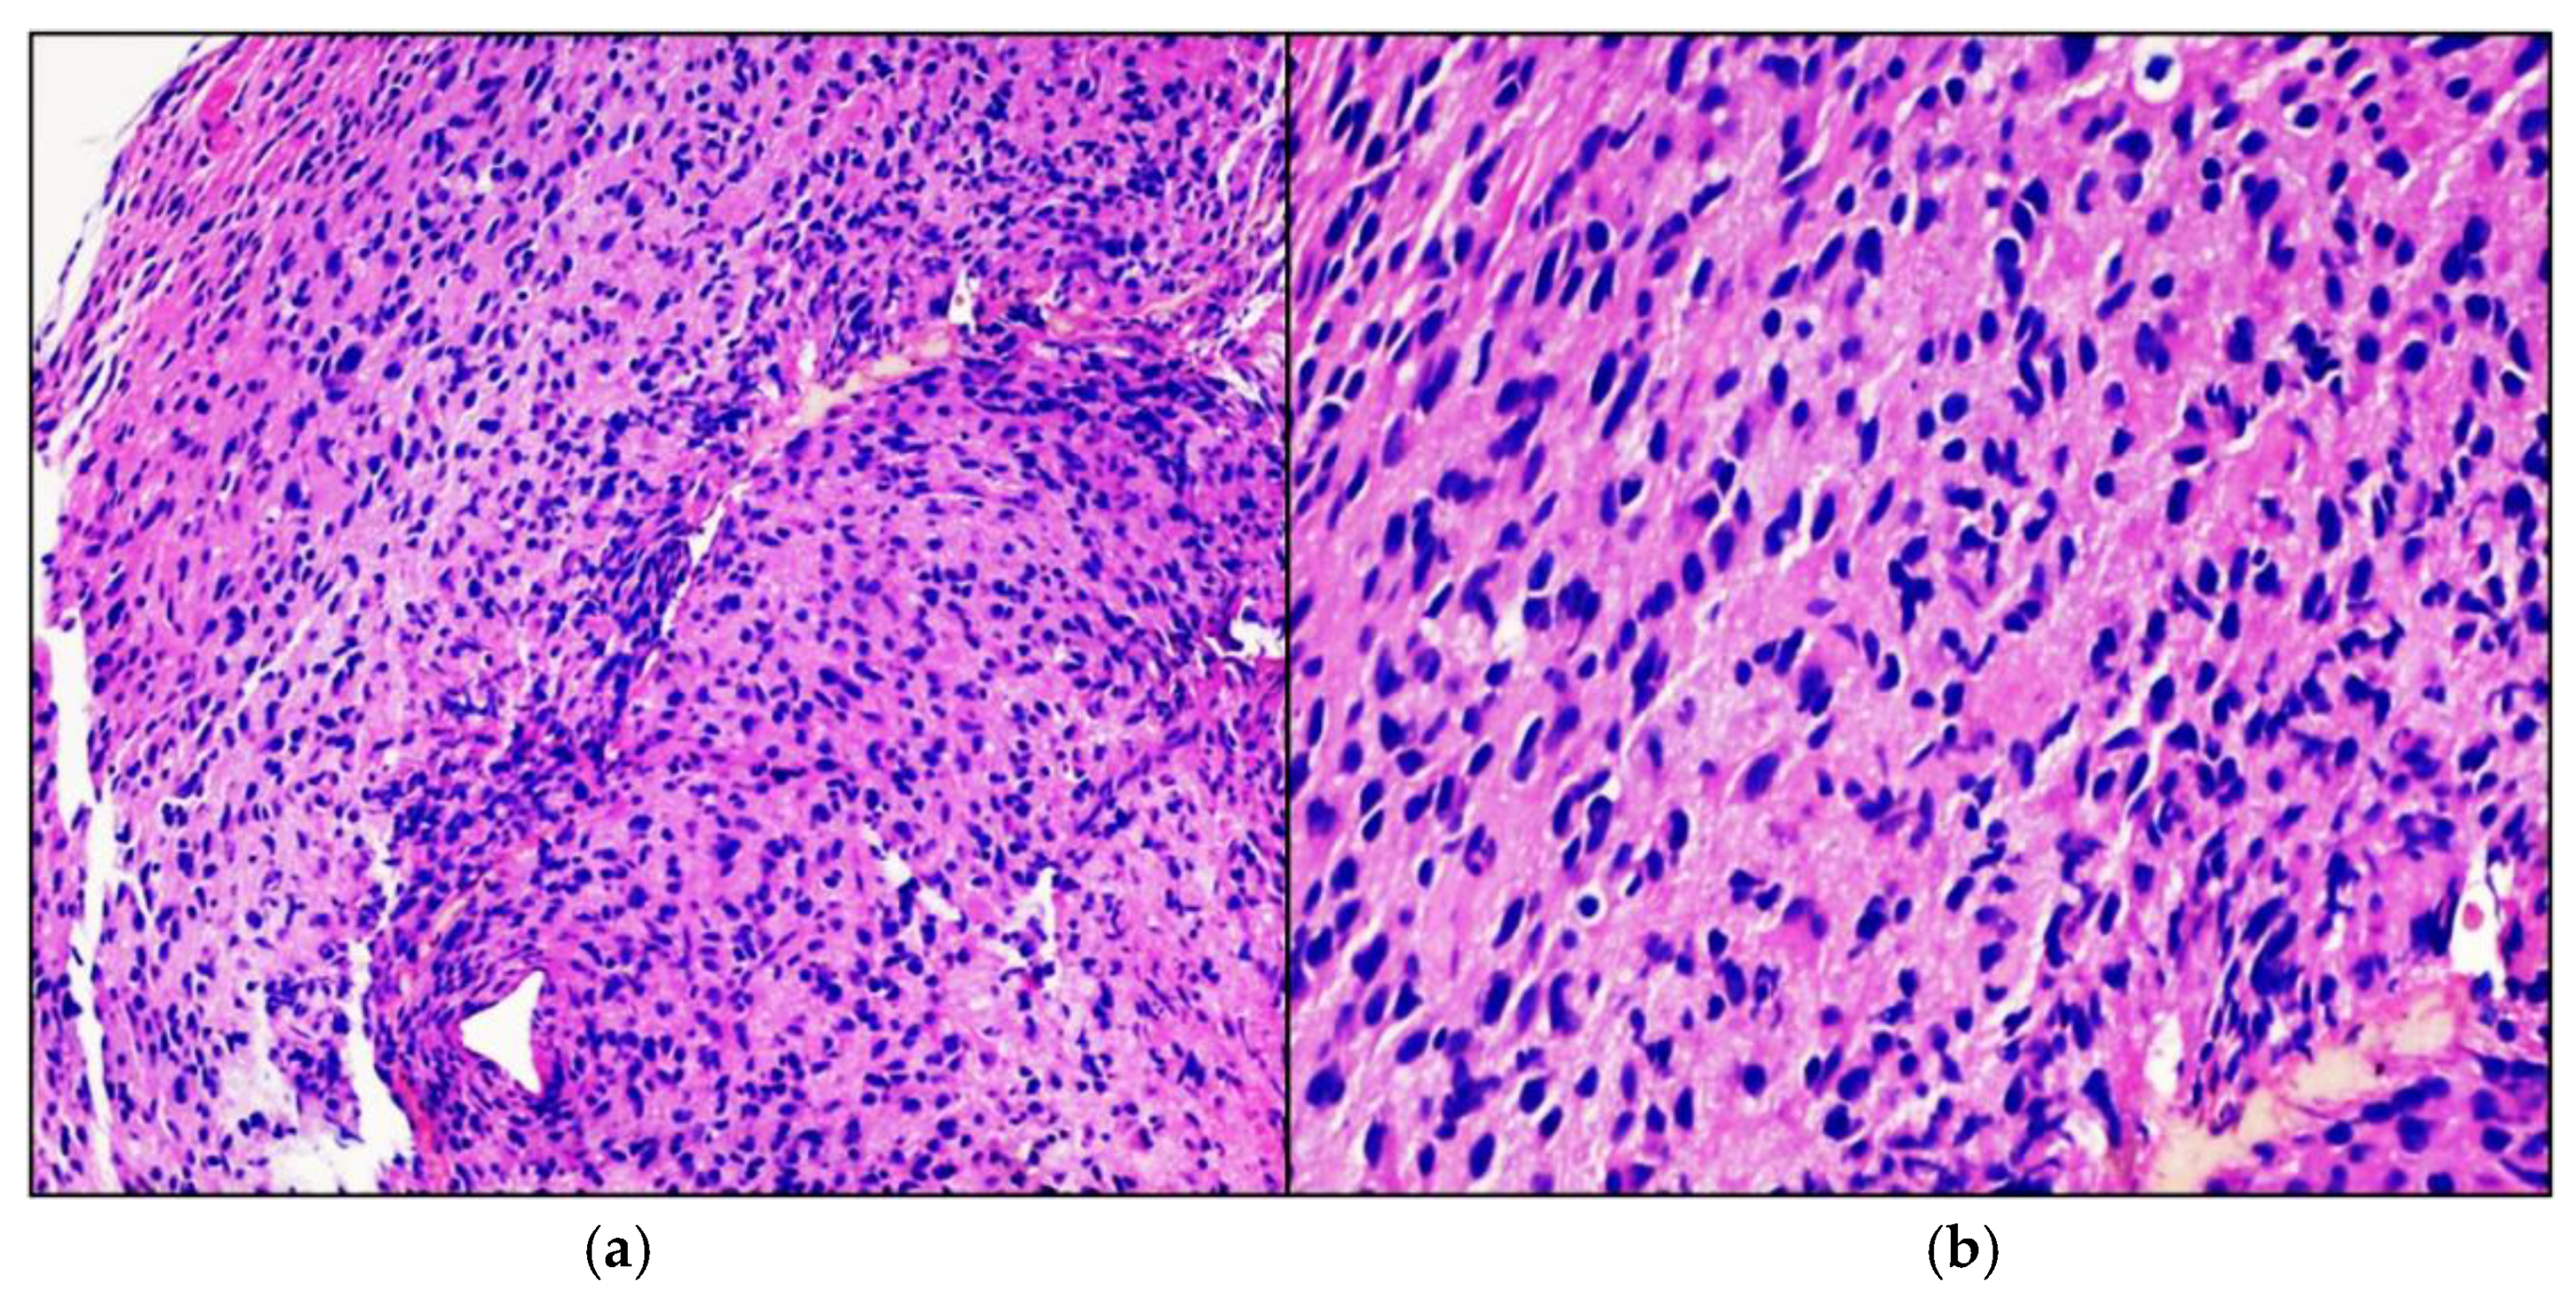

Figure 3.

High-grade glioma. Hematoxylin-eosin-stained photomicrographs with original magnification 100× (a) and 200× (b) showing diffusely infiltrating cigar shaped neoplastic astrocytes with obvious nuclear atypia.